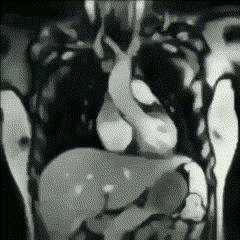

Exploración del sistema cardiovascular